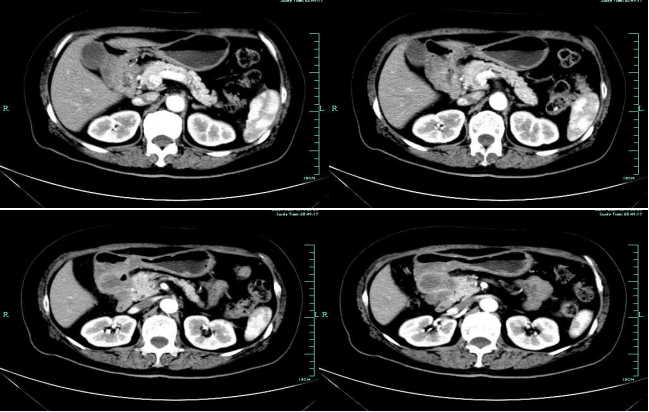

• 第三次FOLFOX+T方案后 B超提示肝转移灶消失

疗效评估:cPR

TOGA研究是第一个使用HER2抑制剂曲妥珠单抗治疗不能手术的局部晚期、复发或转移的HER2阳性胃癌患者的Ⅲ期临床研究。TOGA研究结果显示,IHC2+/FISH阳性或者IHC3+的患者与对照组相比,OS分别为16.0个月和11.8个月(HR为0.65)。曲妥珠单抗联合化疗显著提高了HER2阳性晚期转移性胃癌的治疗缓解率和总体生存率。2012年8月,曲妥珠单抗治疗HER2阳性转移性胃癌适应症在我国获批。对该患者进行病理切片会诊,幸运的是其HER2检测为阳性。随即进行靶向联合化疗治疗,三个周期后,肝转移灶消失,曲妥珠单抗治疗效果显著。九个周期的靶向治疗联合放化疗后,疗效评估cPR,随即行手术治疗。